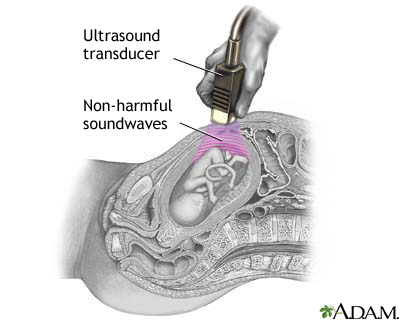

An ultrasound machine makes images so that organs inside the body can be examined. The machine sends out high-frequency sound waves, which reflect off body structures. A computer receives the waves and uses them to create a picture. Unlike with an x-ray or CT scan, this test does not use ionizing radiation.

- A clear, water-based gel is applied to the skin on the area to be examined. The gel helps with the transmission of the sound waves.

- A handheld probe called a transducer is moved over the area being examined. You may need to change position so that other areas can be examined.

- Pregnancy

Some types of ultrasound tests need to be done with a probe that is inserted into your body. Talk to your provider about how your test will be done.